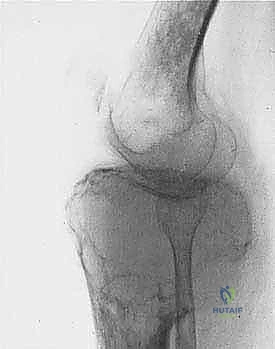

* الساركوما العظمية (Osteosarcoma): الأكثر شيوعاً، تظهر عادة حول الركبة (أسفل الفخذ أو أعلى القصبة).

| حدود الورم في الأشعة | واضحة، محددة بدقة (Sclerotic margin) | غير واضحة، متآكلة (Moth-eaten appearance) |

| اختراق قشرة العظم | نادر جداً | شائع جداً، يمتد للأنسجة الرخوة المحيطة |

1. المفاصل الصناعية الكبيرة (Megaprostheses): مفاصل معدنية متطورة (من التيتانيوم) تُصمم خصيصاً لتعويض العظم المفقود، وتسمح للمريض بالحركة المبكرة.